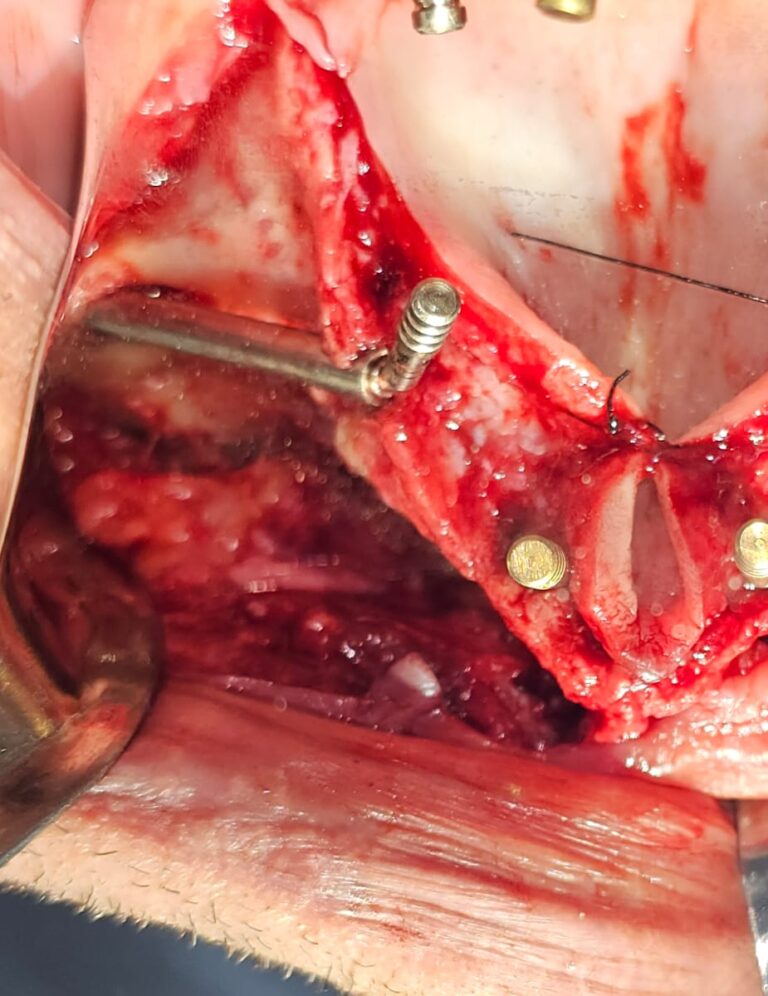

2. Tecniche All-on-4 e All-on-6

3. Grande rialzo del Seno Mascellare

4. Trasposizione dei mentonieri

5. Prelievi ossei e Tecniche Ricostruttive

CORSO DI IMPLANTOLOGIA ZIGOMATICA

1. Impianti Zigomatici

2. Implantologia Nasale e Pterigoidea

3. Gestione della bolla del Bichat